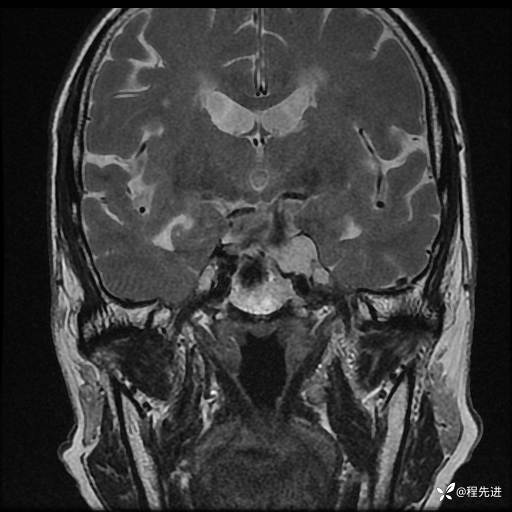

MRI平扫+增强:

T1:

T2:

T1增强: